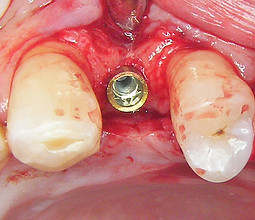

Dettaglio intraoperatorio dell’impianto inserito: il collo viene lasciato esposto palatalmente, la superficie UTM fornirà un adeguato substrato e sostegno per l’incremento dei tessuti molli.